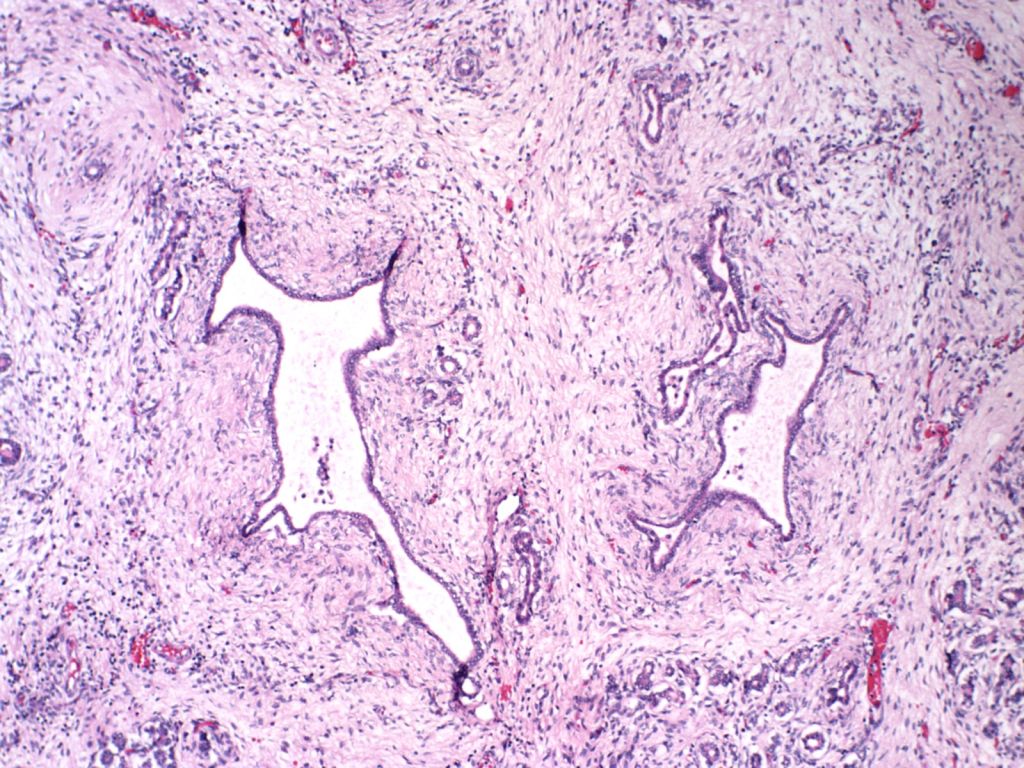

The exocrine pancreas may demonstrate malformations of the duct system such as in Ivemark syndrome of renal-hepatic-pancreatic dysplasia, Meckel Gruber syndrome, and various osteochondrodysplasias[1-3]. (Fig 2, 3) Cystic fibrosis can cause meconium ileus in utero, and may show ductal plugging in the pancreas[4]. In neonates with prolonged cachexia, often seen before total parental nutrition became available, the pancreatic ductules would be dilated with sparse secretion in the lumen.